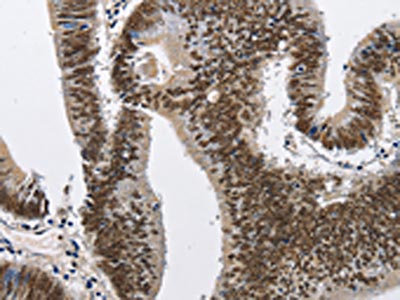

• The image on the left is immunohistochemistry of paraffin-embedded Human colon cancer tissue using CSB-PA098010(CMTM2 Antibody) at dilution 1/60, on the right is treated with fusion protein. (Original magnification: ×200)

• The image on the left is immunohistochemistry of paraffin-embedded Human esophagus cancer tissue using CSB-PA098010(CMTM2 Antibody) at dilution 1/60, on the right is treated with fusion protein. (Original magnification: ×200)